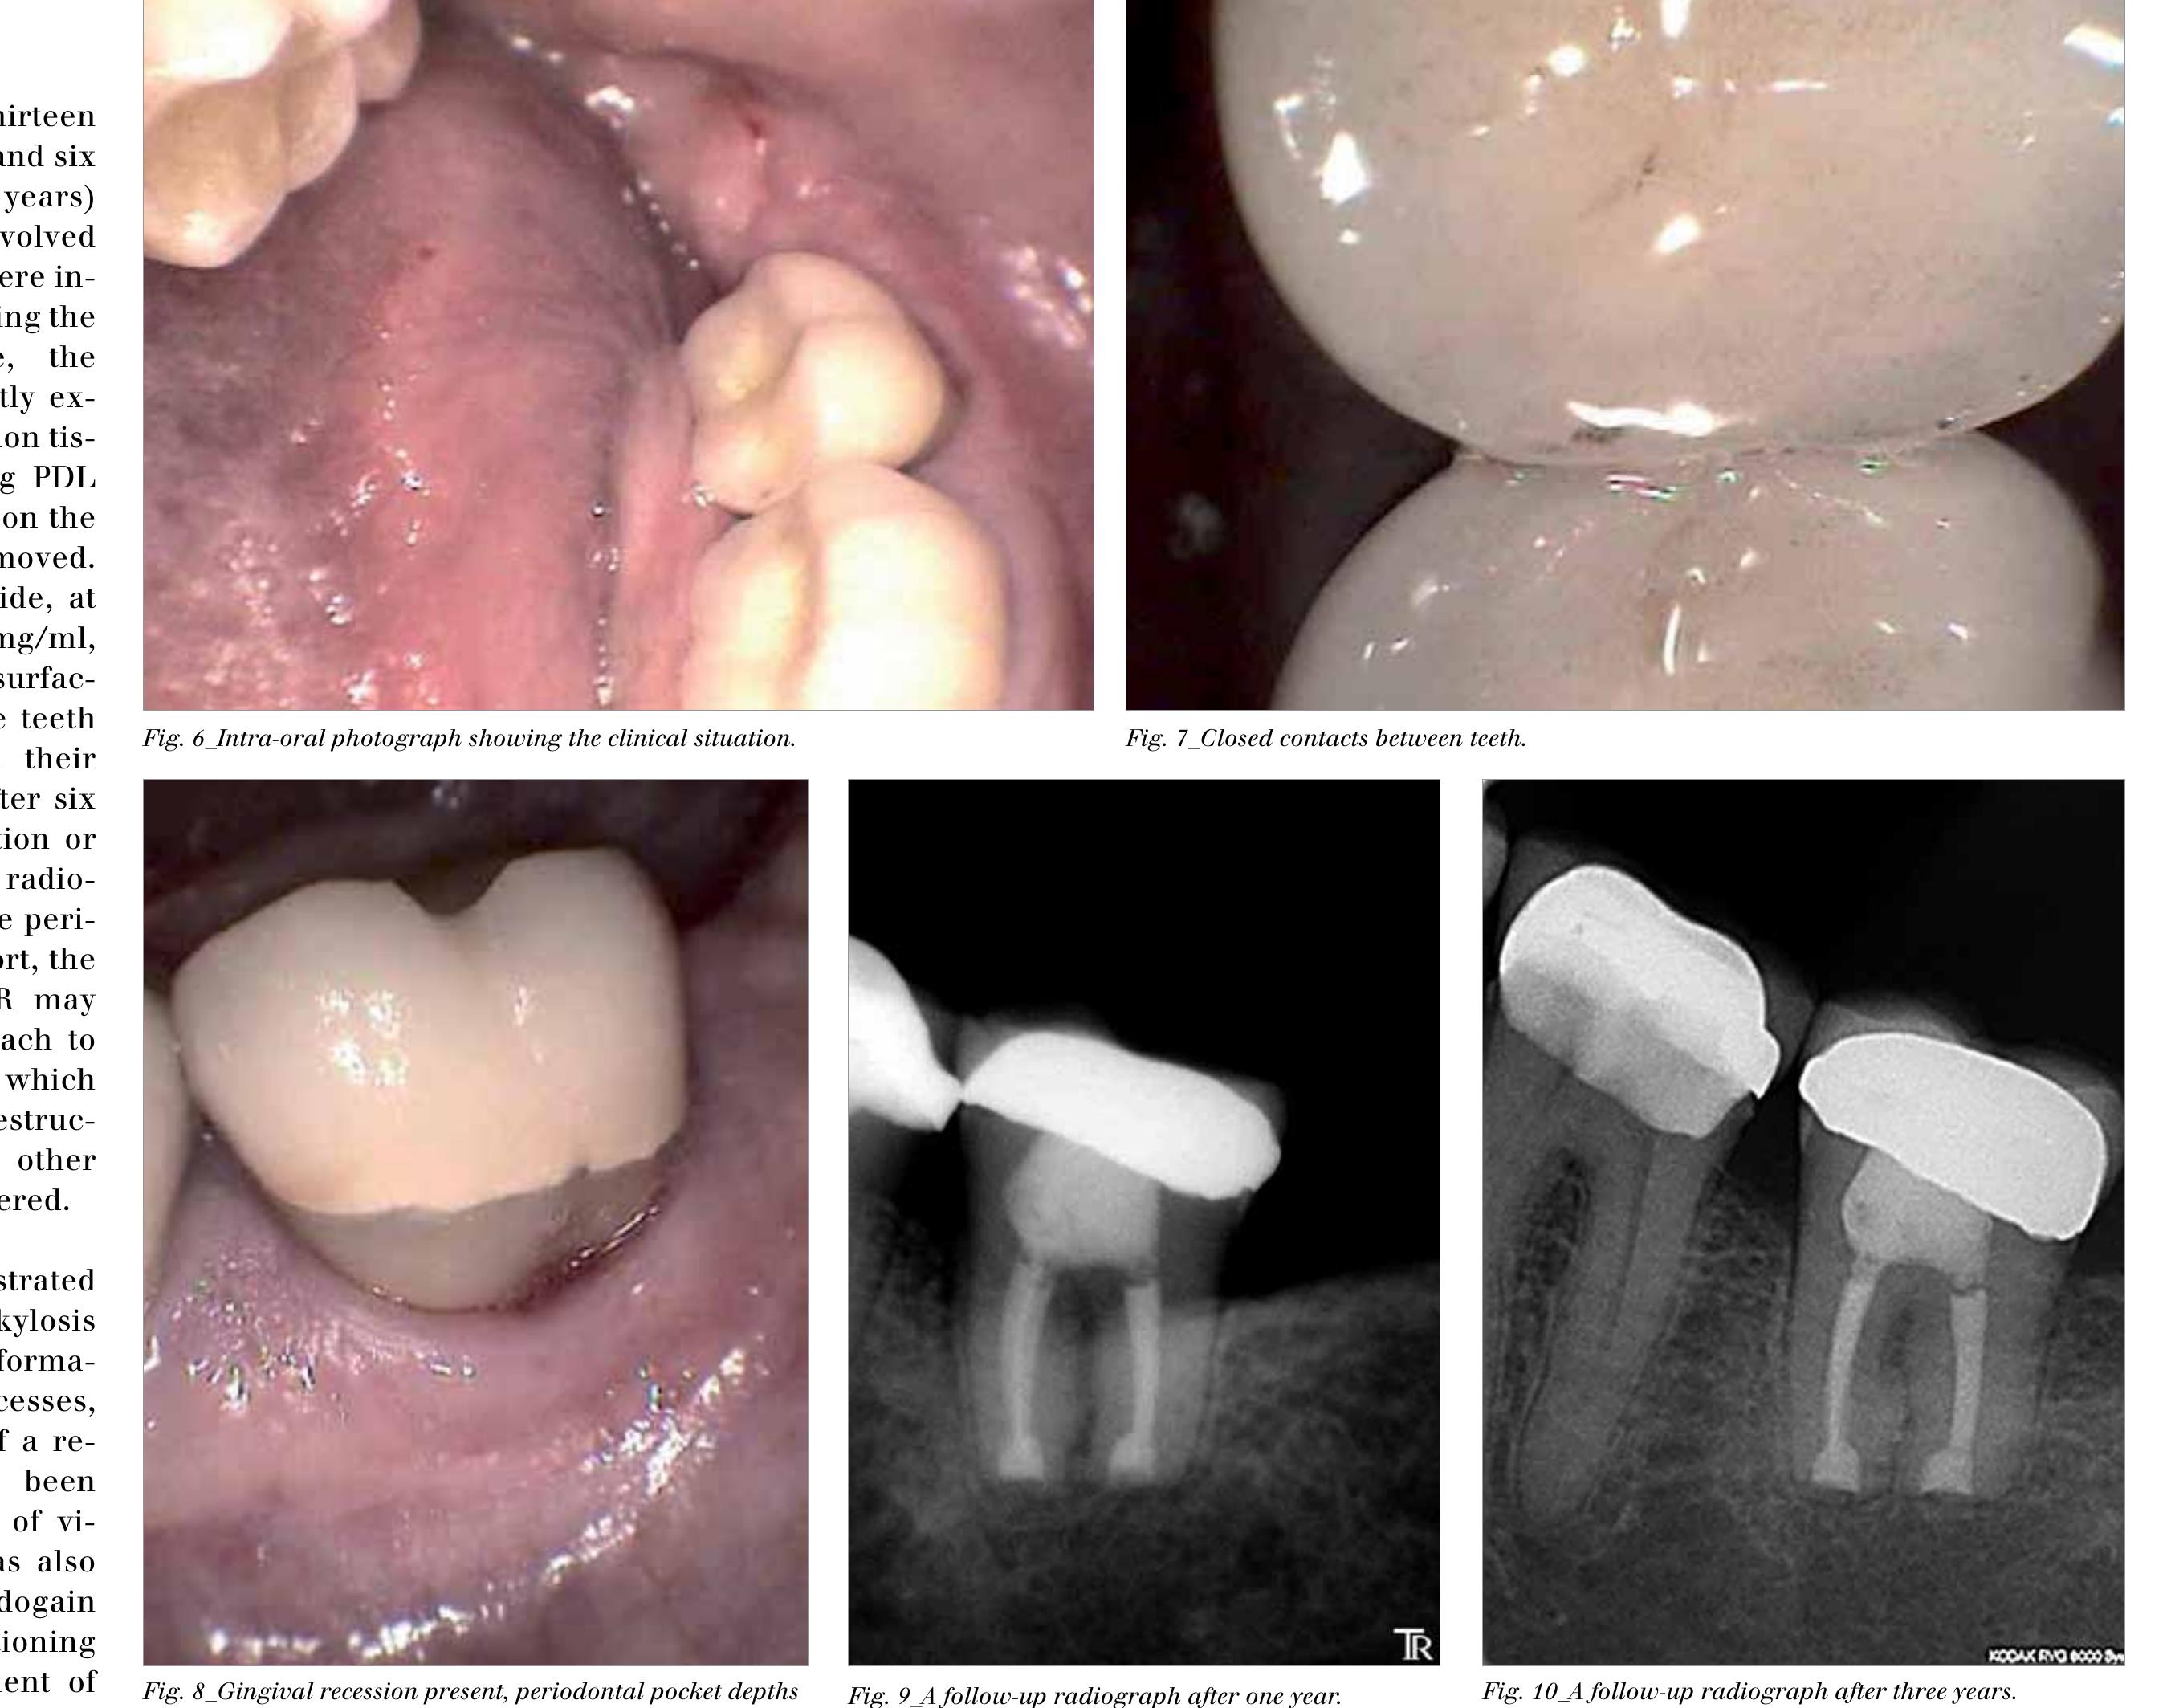

Intentional replantation has been practised for many years as a treatment modality for pulpless teeth. Although the success ratio for intentional replantation is far below that for routine or surgical endodontics, this procedure should be... more

T he functional and esthetic restoration of severely damaged endodontically treated teeth is still a clinical challenge. 1 A typical protocol to restore these teeth is to use posts and cores and a full-coverage crown. However, with the... more